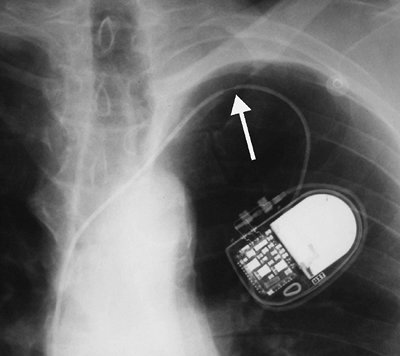

Transvenous Pacemakers

Numerous types of single- and dual-lead pacemakers and combination pacer–defibrillators are available. They are used to treat a variety of dysrhythmias. Accurate interpretation of their appearance on chest radiography requires knowledge of the specific type of pacemaker placed. The three major approaches to insertion of a pacemaker electrode into the heart include epicardial, subxiphoid, and transvenous implantations; transvenous is the most common. With single-lead pacers, the wire is placed into the right ventricle by way of the cephalic, subclavian, or jugular vein. When the lead is wedged into the myocardial trabeculae near the cardiac apex, the lead will be stable and have maximal contact with the endocardial surface. With dual-lead pacers, one lead is generally placed into the right atrium and the other into the right ventricle. It is important to know where the desired placement of leads is for each patient, because placement within the coronary sinus may be accidental or purposeful. After the electrodes are positioned, the generator is placed in a pouch in the subcutaneous tissues of the chest wall or beneath the pectoralis muscle. Biventricular pacemakers are used to treat congestive heart failure. Leads are placed in the right atrium and right ventricle, and a third lead is placed in the coronary sinus for pacing the left ventricle (Fig. 5-18).

Failure of the pacemaker to elicit a ventricular response may be caused by (a) exit block, (b) lead fracture, (c) electrode dislodgment, (d) electrode malposition, (e) myocardial perforation, (f) thrombosis, (g) infection, or (h) battery failure (20). Of these, malpositioning, fracture, and perforation may be recognized on chest radiographs. The leads can be malpositioned within the coronary sinus, and in this case the catheter often appears to be ideally positioned on the frontal radiograph but

P.71

is directed posteriorly rather than anteriorly on the lateral projection. Approximately 2.7% of electrodes will fracture (21), generally near the pulse generator, at sharp bends in the lead wires, at the point of venous entry, or where the lead is embedded in the cardiac muscle (Figs. 5-19, 5-20, 5-21). If the insulating sheath holds the ends of a fractured lead in close proximity, the fracture may not be readily visible on a radiograph. Tight anchoring ligatures at the venous entry site can produce lucency of the lead, giving the false appearance of a fracture.